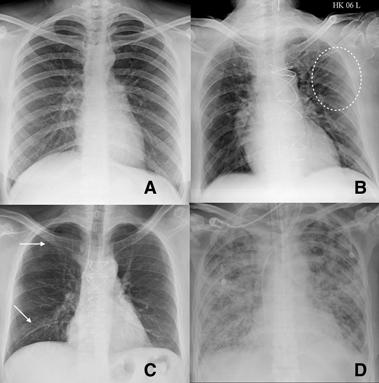

Fig 2 — CXR (A) and CT (B& C) images of a 50-year-old man with 6 days history of fever and dry cough. RT-PCR test was positive. CXR shows bilateral diffuse opacities, with a more opaque patch in the right lower zone (white arrow). The corresponding CT shows the true extent of the disease (black arrows). Images reproduced with permission from Covid-19 Database of the Fleischner Society.

Fig 3 — CXR images from two different patients with COVID-19 showing peripheral areas of consolidation bilaterally in A and unilaterally in B (arrows). Images reproduced with permission from Covid-19 Database of the Societa Italiana di Radiologia Medica e Interventistica.